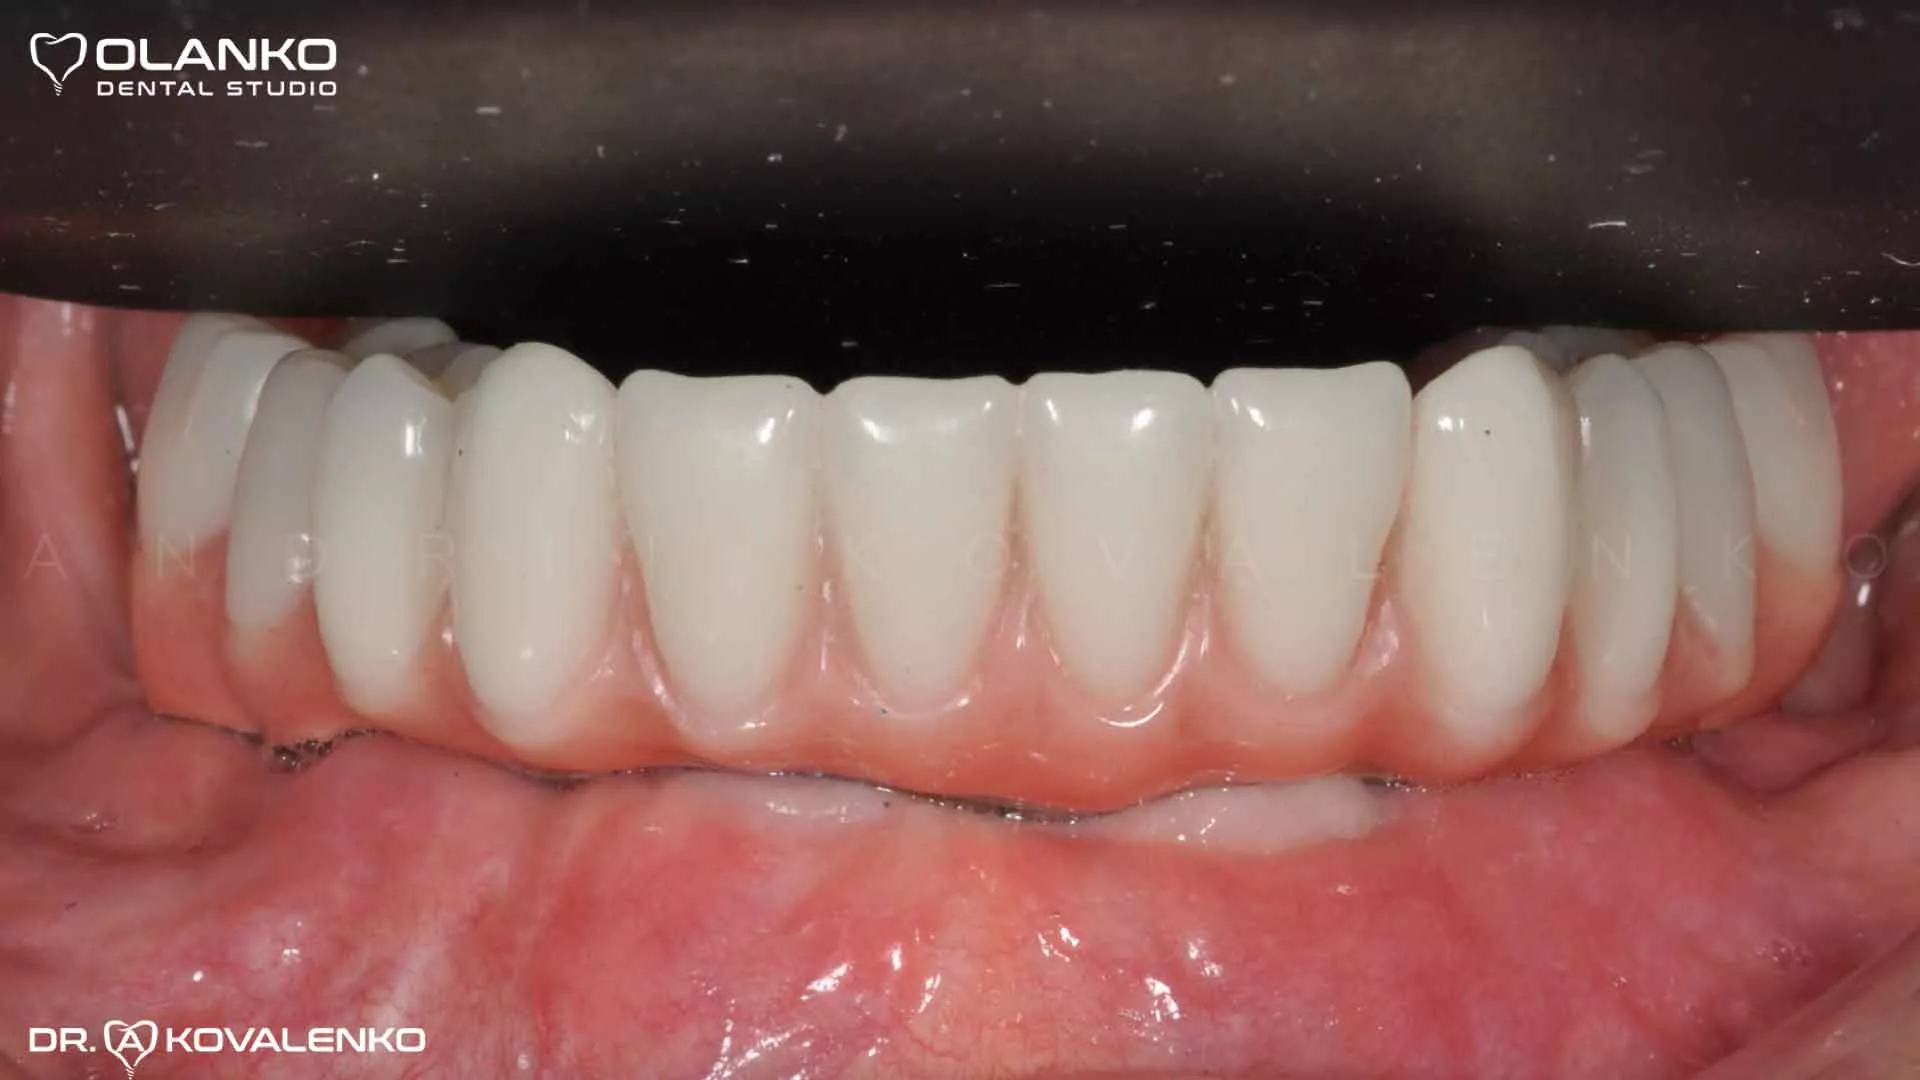

Приклад протезування по технології All on 4 беззубої нижньої щелепи

Фото після установки та приживлення імплантів

Фото після установки зубного протеза з опорою на 4 імпланта